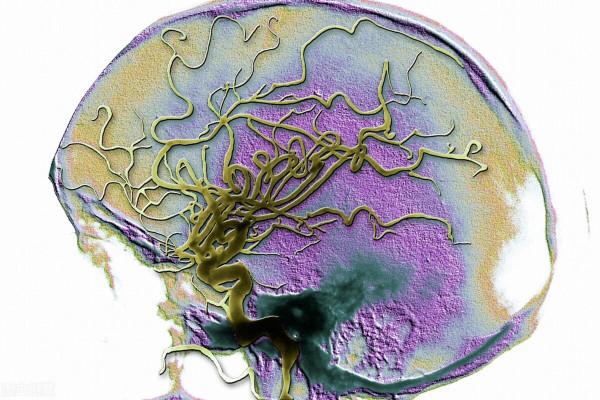

那天傍晚時分,患者家屬給我打電話,說是病人1小時前突然頭痛,左側肢體無力,言語也不清,還有噁心嘔吐。我一聽,這是腦卒中了。趕緊查頭顱CT、住院吧!

一做頭顱CT,腦幹出血。

腦幹在什麼地方,腦子通往脊髓的部位,管血壓、心跳、呼吸的部位,生命中樞啊!這個地方很小,稍微有點兒出血就會壓迫腦組織。生命中樞的腦組織受壓,生命堪憂了!

患者家屬說,患者因為近期血壓平穩,想著自己換換降壓藥。這一換藥,血壓就波動了,下午血壓升到140/100mmHg以上。雖說這個血壓不算太高,可架不住患者的血管早已是千瘡百孔。血壓一高,早已受損的腦血管破裂,還是腦幹部位,腦幹出血了。

這位患者當時還清醒,很快就進入了昏迷。因為腦出血後腦組織損傷,接下來就會腦水腫,腦殼裡的壓力、也就是顱內壓就會升高,壓迫腦組織,受壓的腦組織功能就受影響了。